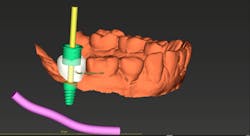

As my implant experience grows, I find myself ordering CBCT-based surgical guides more often. When used properly, a guide can make the procedure shorter, safer, and less stressful for both the doctor and the patient. I am a firm believer in placing screw-retained restorations whenever possible; preplanning my surgery with a digital wax-up and using a surgical guide ensures that the implant is in the optimum restorative position (figures 4–5). Even though an experienced surgeon with top-notch clinical skills can place an implant in an acceptable position most of the time, there is no way they can place it in a better position than with a surgical guide. They can only hope to do as well—not better.